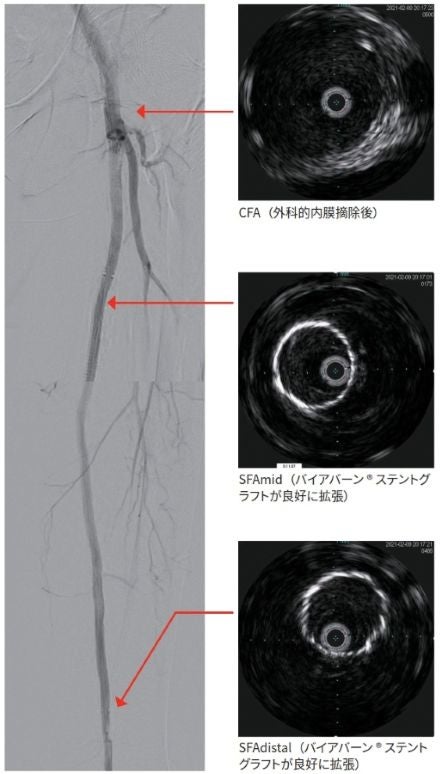

その後バイアバーン® ステントグラフトの留置を試みた。バイアバーン® ステントグラフトをdistal に径6.0/長150 mm、proximal に径6.0 mm / 長250 mmを留置し、径6 mm / 長150 mmのバルーンで後拡張し、アンギオとIVUSにて良好な開存を確認した後、手技を終了した(図3)。

バイアバーン® ステントグラフトの治験や過去の報告2からも、バイアバーン® ステントグラフトをヘルシーランディングし、病変をフルカバーすることによって良好な成績が示されていることから、今回の症例においても、SFAのproximal にはステントのランディングゾーンがなく、外科的内膜摘除術を行うことでヘルシーランディングを可能とし、またIVUSと造影にて病変確認をしっかり行いながらフルカバーし留置することができた。またバイアバーン® ステントグラフトの特性からステント展開時にマイグレーションを起こしにくく、ステントエロンゲーションも生じにくい設計であるため、ストレスなく留置することができると感じている。